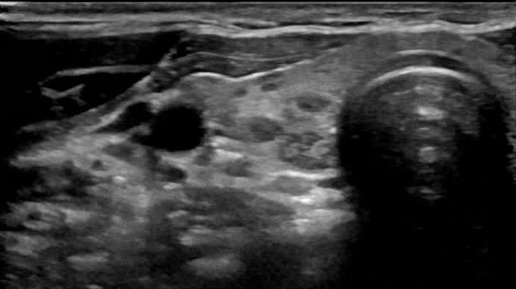

Видео к статье "Стратификация узлов щитовидной железы. TI-RADS-3" https://dzen.ru/a/Zv4svErHVi-eImKZ

Ультразвуковые находки от врача УЗД Зорина Я.П.